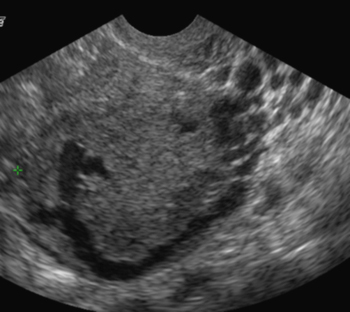

Varices pelviennes (Cliché : Dr. C. TALMANT)